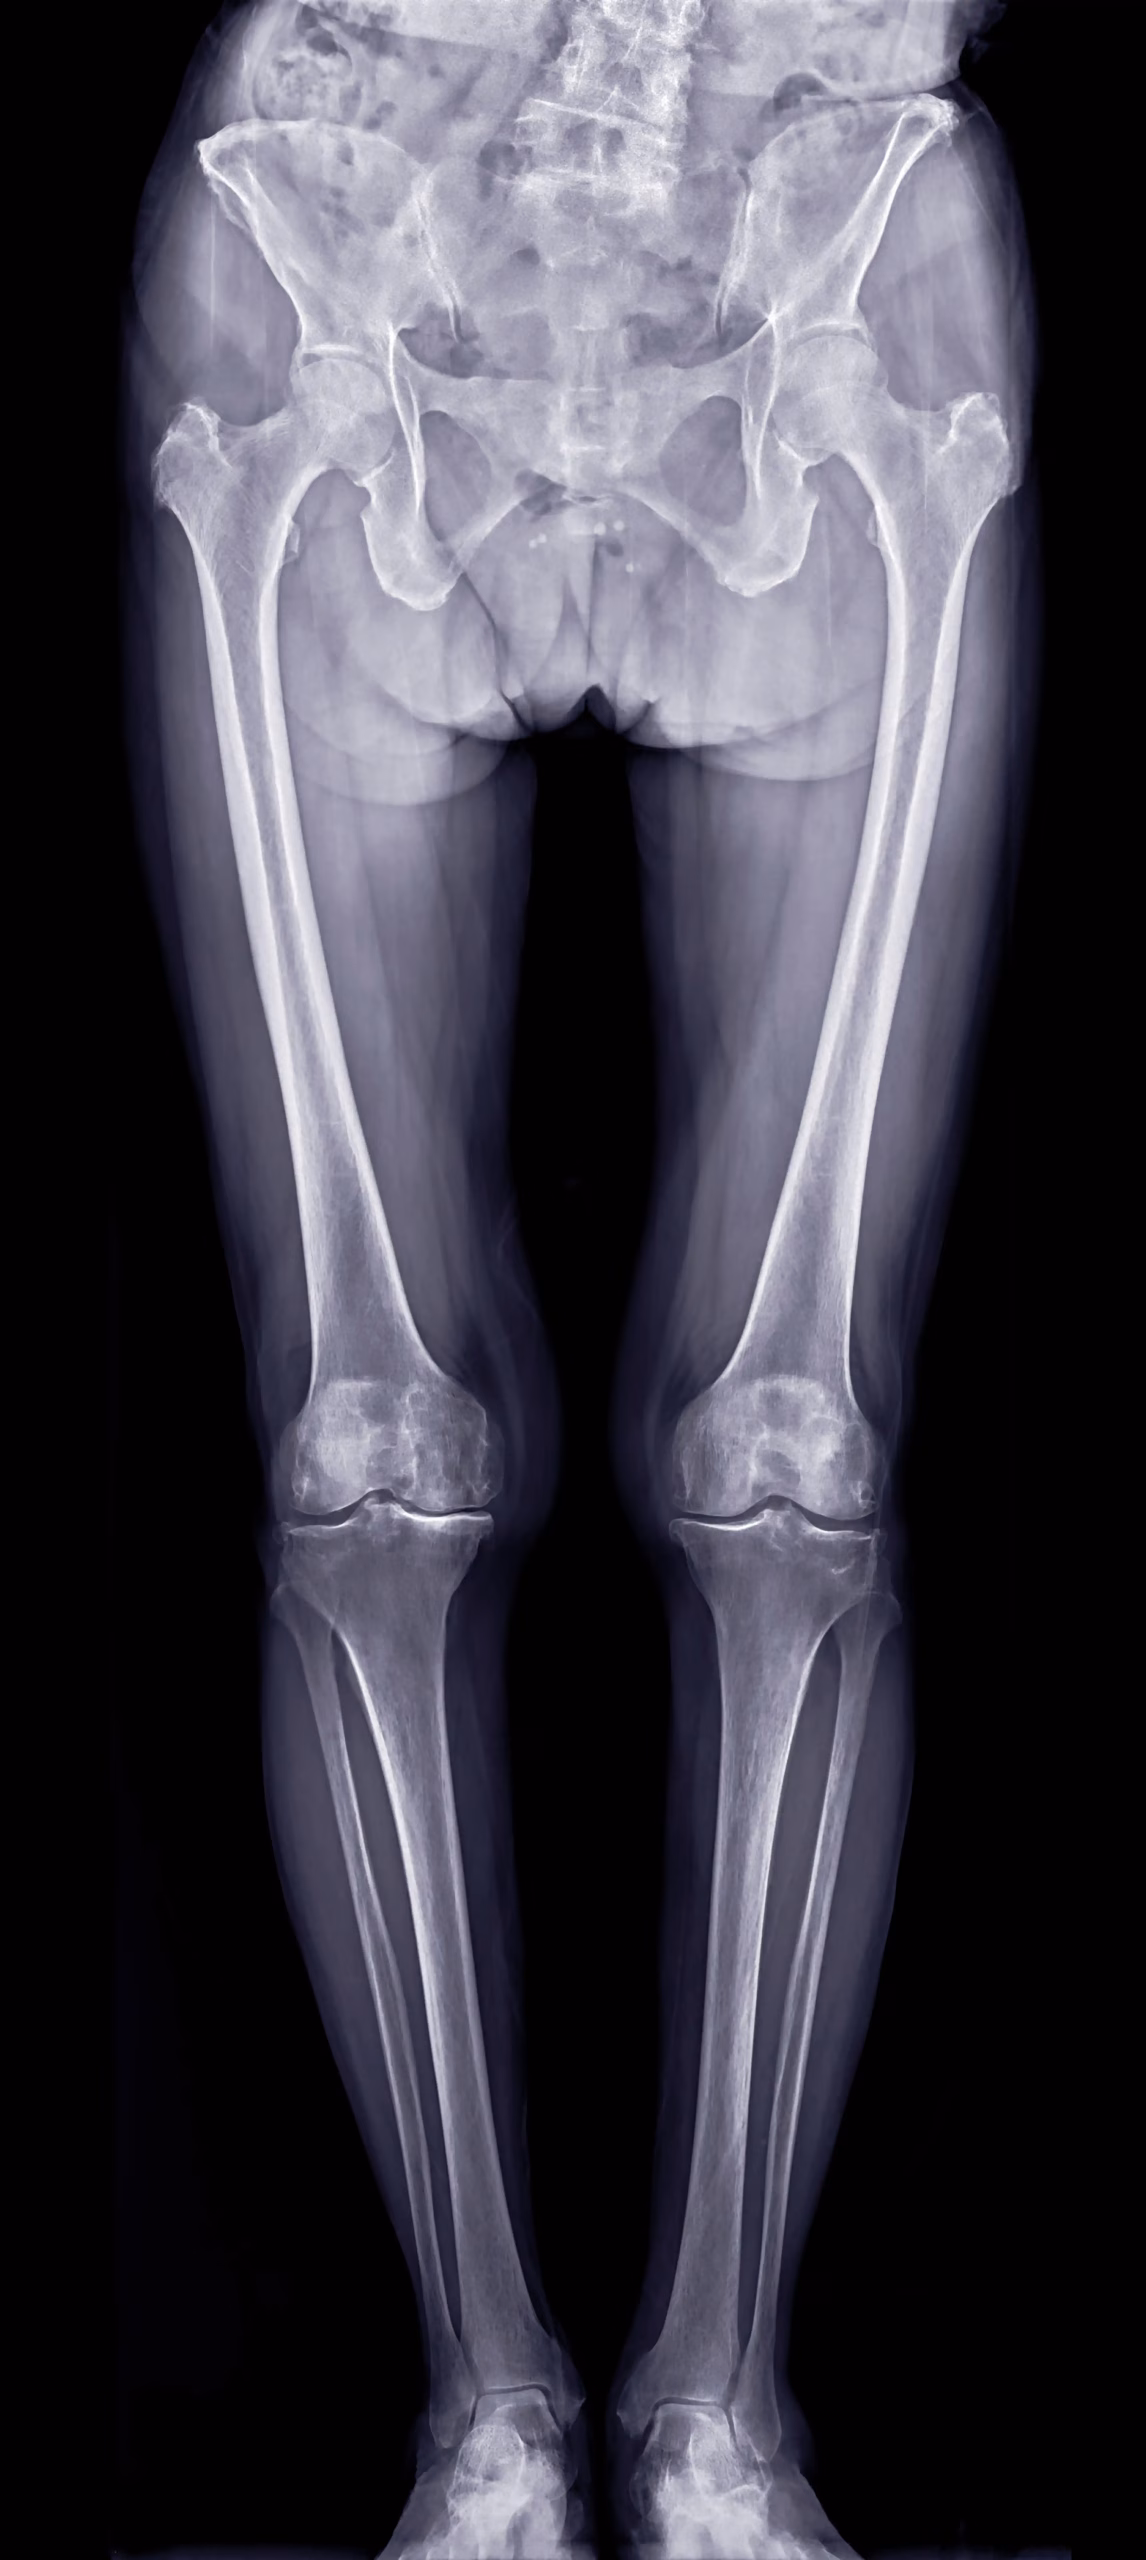

🮽 Pangonogramă / Orto-leg

• Ax membre inferioare complet (șold–genunchi–gleznă)

• Inegalități de membre, planificare pre/post-operatorie

Ce este pangonograma și când este indicată?

Pangonograma (Orto-leg) este radiografia panoramică a membrului inferior complet — șold, genunchi și gleznă într-o singură imagine. Permite măsurarea axului mecanic al membrului inferior și identificarea inegalităților de membre. Este indicată preoperator (protezare șold/genunchi, osteotomii) și în monitorizarea postoperatorie, precum și în evaluarea devierilor de ax (varus/valgus).